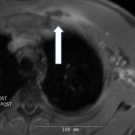

The authors report a case of Streptococcus sanguinis bacteremia that led to the discovery of invasive colorectal adenocarcinoma.

05/18/2020